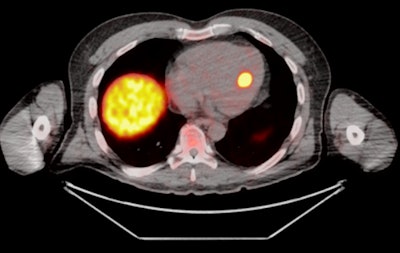

![Axial Ga-68 DOTATATE PET/CT image for the same patient demonstrates the focal tracer uptake localized to the interventricular septum (maximum standardized uptake value [SUVmax] = 24).](https://img.auntminnieeurope.com/files/base/smg/all/image/2020/10/ame.2020_10_27_16_51_9149_2020_10_27_mol_insider_Renfrew_figure2.png?auto=format%2Ccompress&fit=max&q=70&w=400)

"While hepatic and nodal metastases are commonplace at the time of NET diagnosis, cardiac metastases are found much less frequently," explained Renfrew, who is a postgraduate year 5 (PGY-5) radiology resident. "The diagnostic criterion of cardiac metastasis is focal tracer uptake in the myocardium."

A total of 16 cardiac lesions were located in the left ventricle, eight were in the interventricular septum, and five were in the right ventricle.

The average SUVmax of these lesions was 9.2 (range, 2.6-24.1), and the Krenning score was 2-4. The average SUVmax of blood pool was 1.2 (range, 0.5-2.4). The average lesion to blood pool SUV ratio was 8.3 (range, 2.6-18.2).